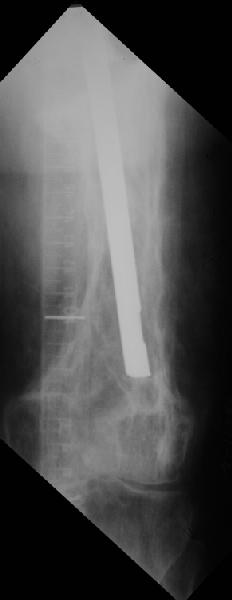

Еще один пример. Пациентка с юга России, прислала рентгенограммы через год. На сегодня прошло 2 г. 8 мес. после операции. Несмотря на не очень убедительный процесс сращения, пациентка ходит. Учитывая остеопороз при Педжете, решили, что динамизировать вообще не нужно.